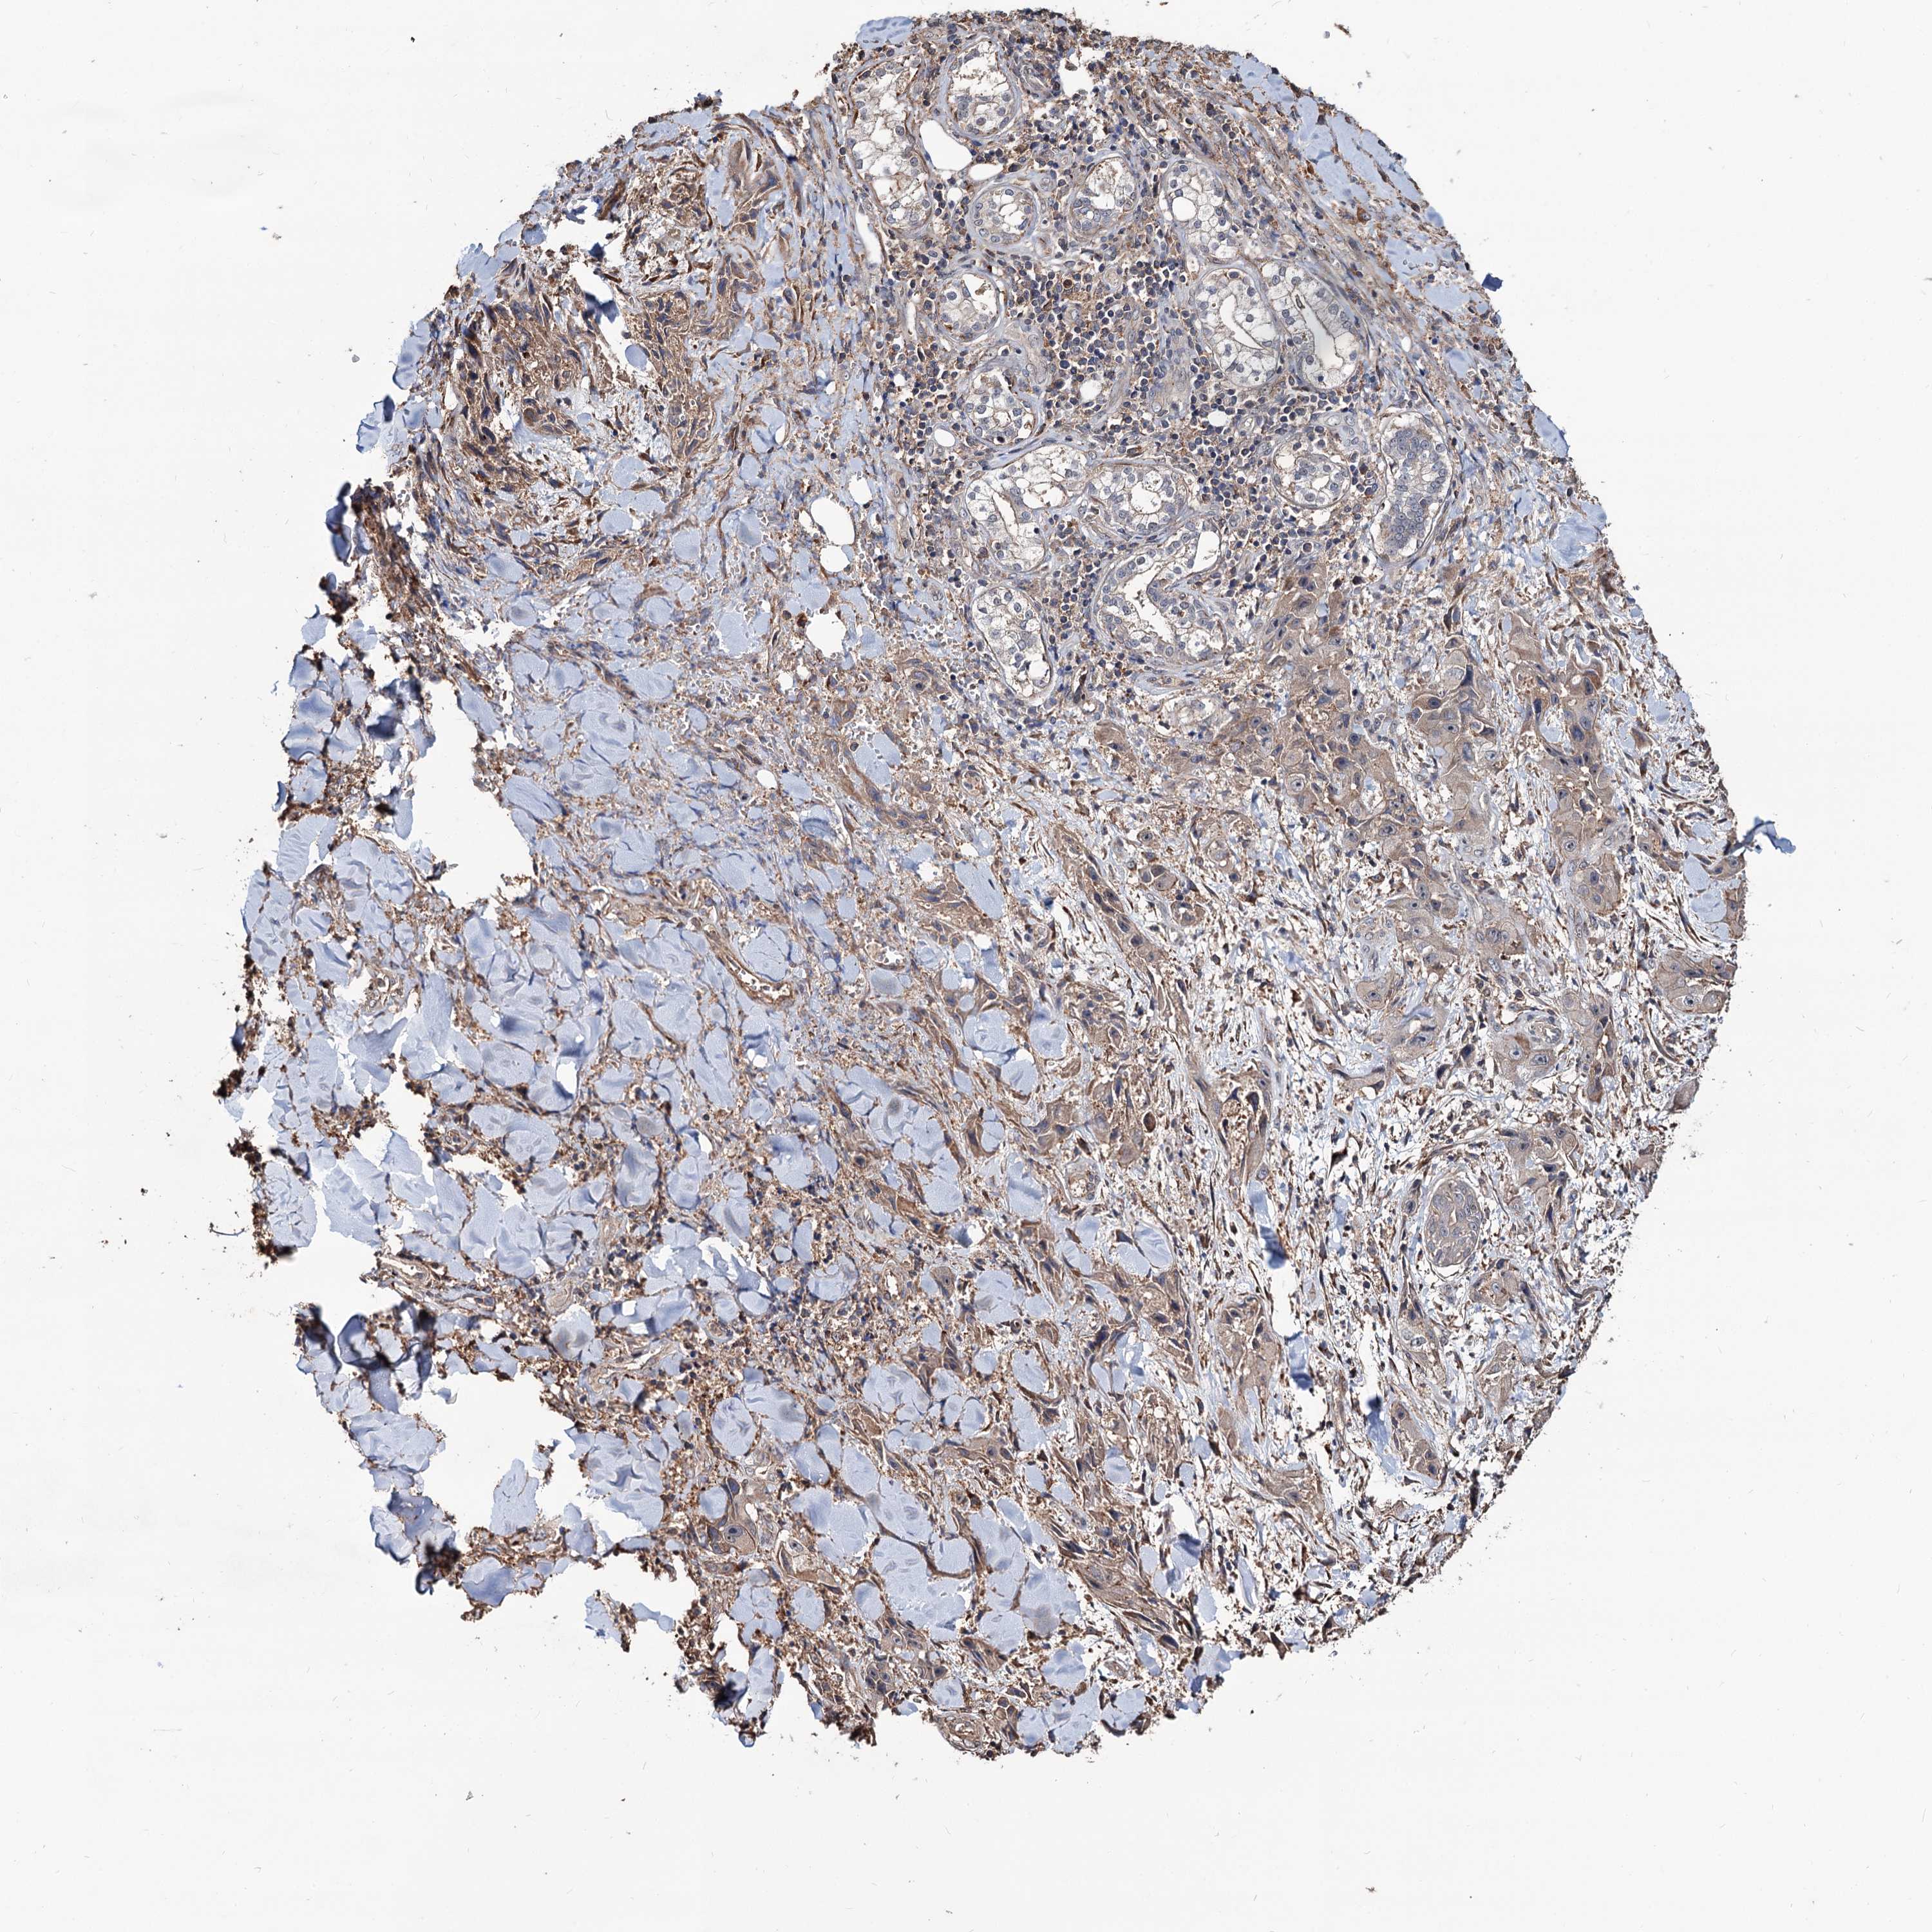

SKIN CANCER - Protein expressioni

A mouse-over function shows sample information and annotation data. Click on an image to view it in a full screen mode. Samples can be filtered based on level of antibody staining by selecting one or several of the following categories: high, medium, low and not detected. The assay and annotation is described here.

Each image is clickable and will lead to virtual microscopy that enables deeper exploration of all samples and also displays staining intensity scores, fraction scores and subcellular localization as well as patient and tissue information for each sample.

Antibody HPA038856

Staining

Medium

Intensity

Moderate

Quantity

75%-25%

Location

Cytoplasmic/membranous

Squamous cell carcinoma, NOS